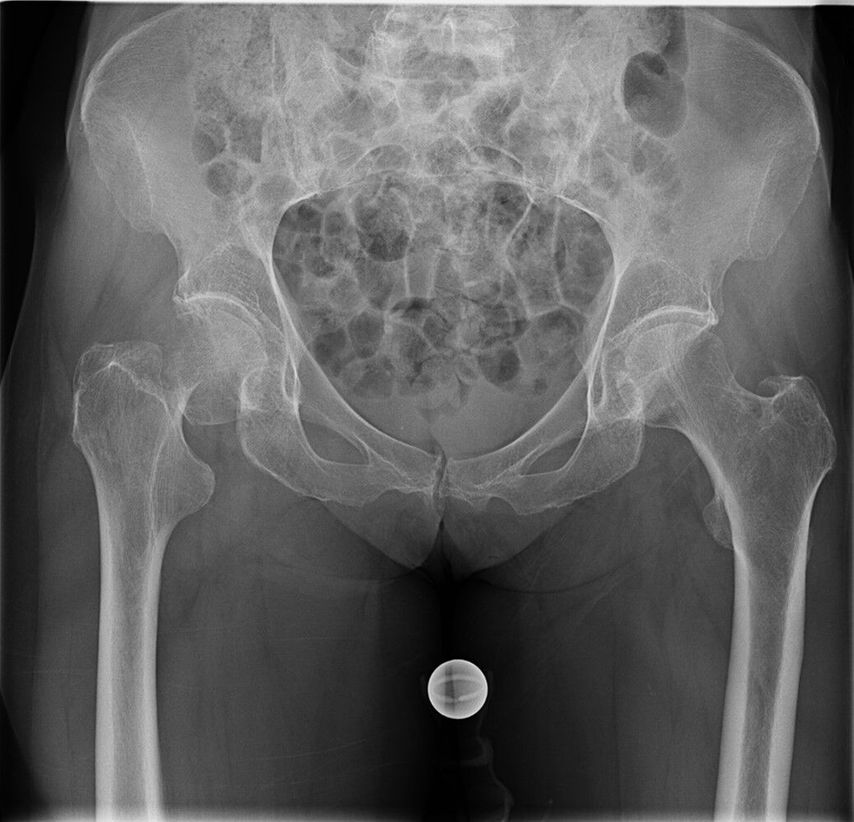

Seit 2021 werden in der Klinik für Unfallchirurgie und Orthopädie des Johannes Wesling Klinikums, Minden, ältere Patienten, die sich eine dislozierte mediale Schenkelhalsfraktur Garden III oder IV zugezogen haben, mit einer zementierten Kurzschaftprothese versorgt. Als Kopf wird entweder eine unipolare Pfanne oder eine zementfreie Pfanne implantiert. 2023 und 2024 wurde bei insgesamt 174 Patienten eine zementierte Kurzschaftprothese über einen Watson-Jones-Zugang in Rückenlage implantiert. Das Durchschnittsalter lag über 80 Jahre. Es wurden mehr Frauen als Männer behandelt (67,2% weiblich, 32,8% männlich). Fast 70% der Patienten fielen in die ASA-Klassifikation Grad 3 (1,1% ASA 1; 21,3% ASA 2; 70,1% ASA 3; 6,9% ASA 4; 0,6% ASA 5). Insgesamt 84,5% der Patienten erhielten eine Hemiendoprothese, während 15,5% mit einer Totalendoprothese versorgt wurden (Abb. 3,4). Nach der postoperativen unfallchirurgischen Behandlung wurden die Patienten entweder in eine geriatrische Klinik innerhalb oder ausserhalb des Krankenhauses verlegt oder es erfolgte eine stationäre Anschlussrehabilitation. Bis zum Zeitpunkt der Entlassung musste bei vier Patienten aufgrund einer prolongierten Wundsekretion eine Wundrevision durchgeführt werden. Im Rahmen der postoperativen Mobilisation kam es bei einem Patienten zu einer Luxation, die nach Reposition konservativ behandelt wurde. Die operierten Patienten werden aktuell zur Nachuntersuchung eingeladen.

Abb. 3: 81-jährige Patientin mit nach Sturz dislozierter Schenkelhalsfraktur Garden IV rechts